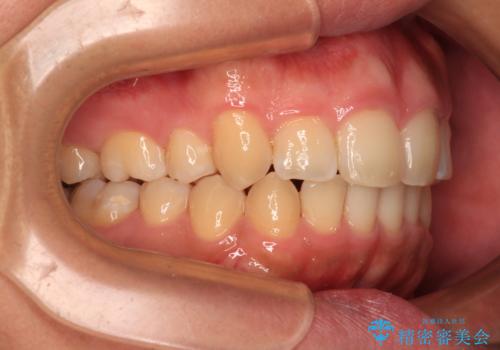

- 学生時代に抜歯矯正した歯列が後戻りしてきたとのことで来院された患者様です。

舌の突出癖が原因で上顎前歯が前方に移動したと考えられたため、舌のトレーニングを徹底して行っていただきながら、後戻りを解消していくこととしました。

マウスピース矯正でもワイヤー矯正でも対応可能でしたが、患者様の希望によりワイヤー装置による矯正治療を行うこととしました。

ワイヤー矯正ということで、上顎大臼歯を後方に移動するための補助装置を併用して、積極的に前歯を引っ込めていくこととしました。